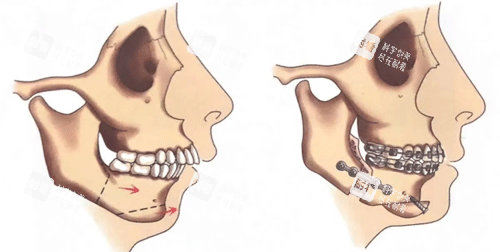

正颌手术是针对牙颌面畸形的外科治疗方法,它通过精细截断上颌骨、下颌骨或周围颧骨,将这些骨骼移动到预期的正常位置,从而矫正地包天、小下颌、脸歪等问题。

这是更常用的上颌骨手术方式,适用于上颌骨前后向、垂直向或横向发育异常的患者。

手术通过在上颌骨特定位置截骨,可以整体移动上颌骨,解决上颌前突、后缩或不对称等问题。

2. 下颌升支矢状劈开截骨术(SSRO)

这是矫正下颌畸形更常用的手术方式,尤其适用于下颌前突或后缩的患者。

3. 水平截骨颏成形术

专门针对颏部(下巴)畸形设计的手术,可以改变下巴的前后位置、垂直高度和左右对称性。